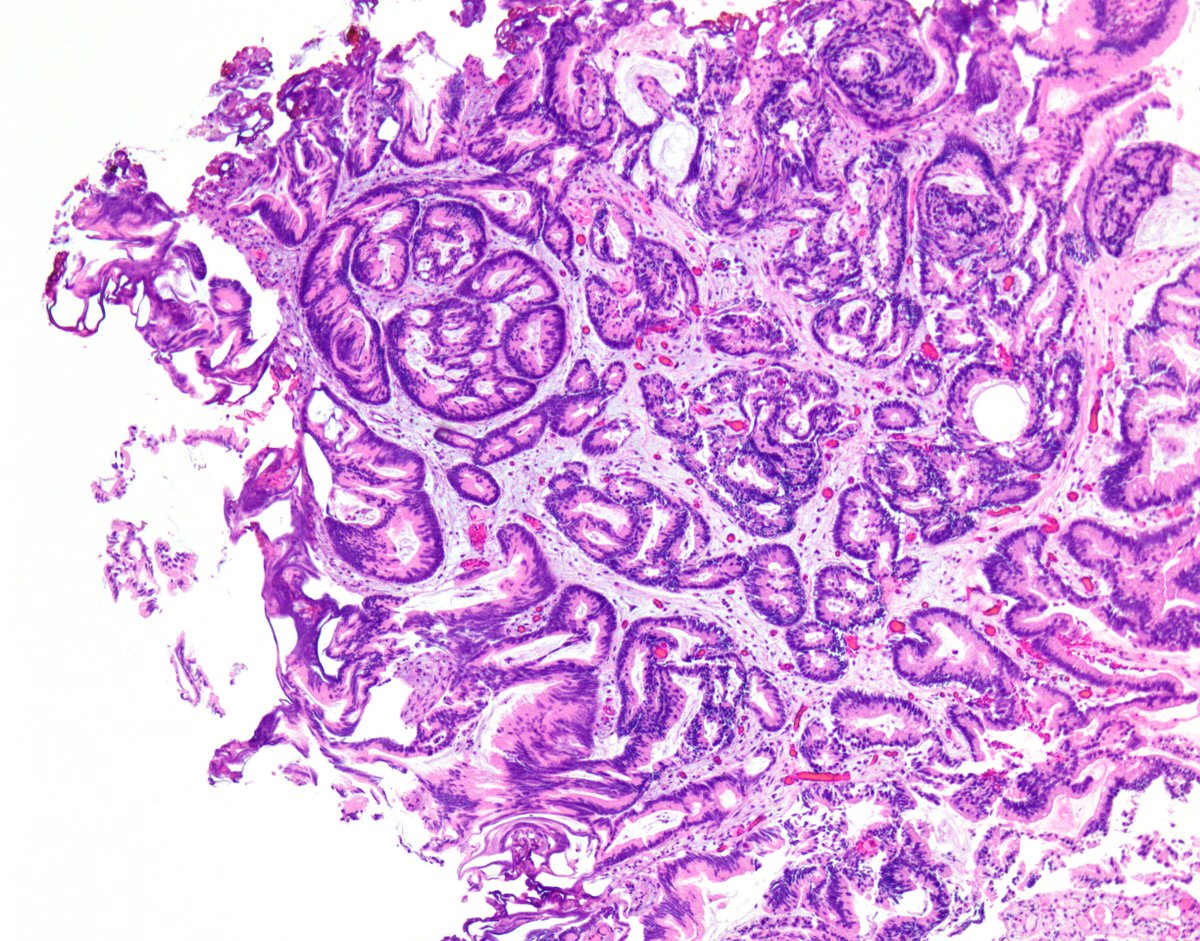

Single focus in well sampled #prostate (including snapshots of levels) How far would you go ASAP vs PCA Gleason Score? #GUPATH #pathology #pathres

Thanks to all who responded! I favored minute focus of PCA 3+4, with comment that assessing percentage of Gl4 is difficult in small foci ⚡️🛑 Sharing to highlight the spectrum of interpretation for small foci like this & danger of over-Gleason scoring them #gupath #pathology